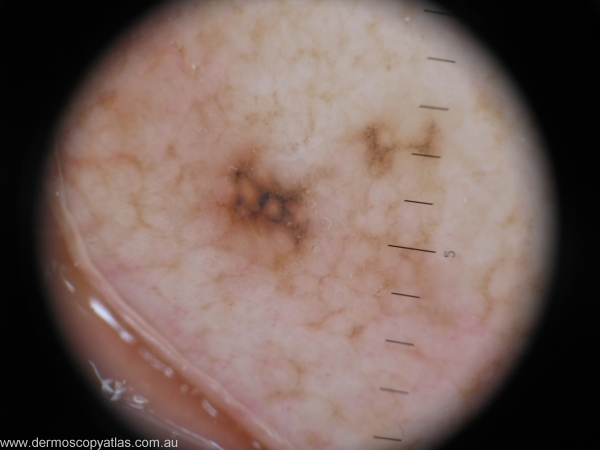

Case 3 42 year old Golf course curator. Left pinna lesion noted on routine skin check. Patient unaware of lesion.

Question: What is your provisional diagnosis? Consider Atypical spitz, Pigmented IEC, Lentigo maligna, Solar lentigo and Compound nevus with regression.

Answer: Compound naevus showing focal regression